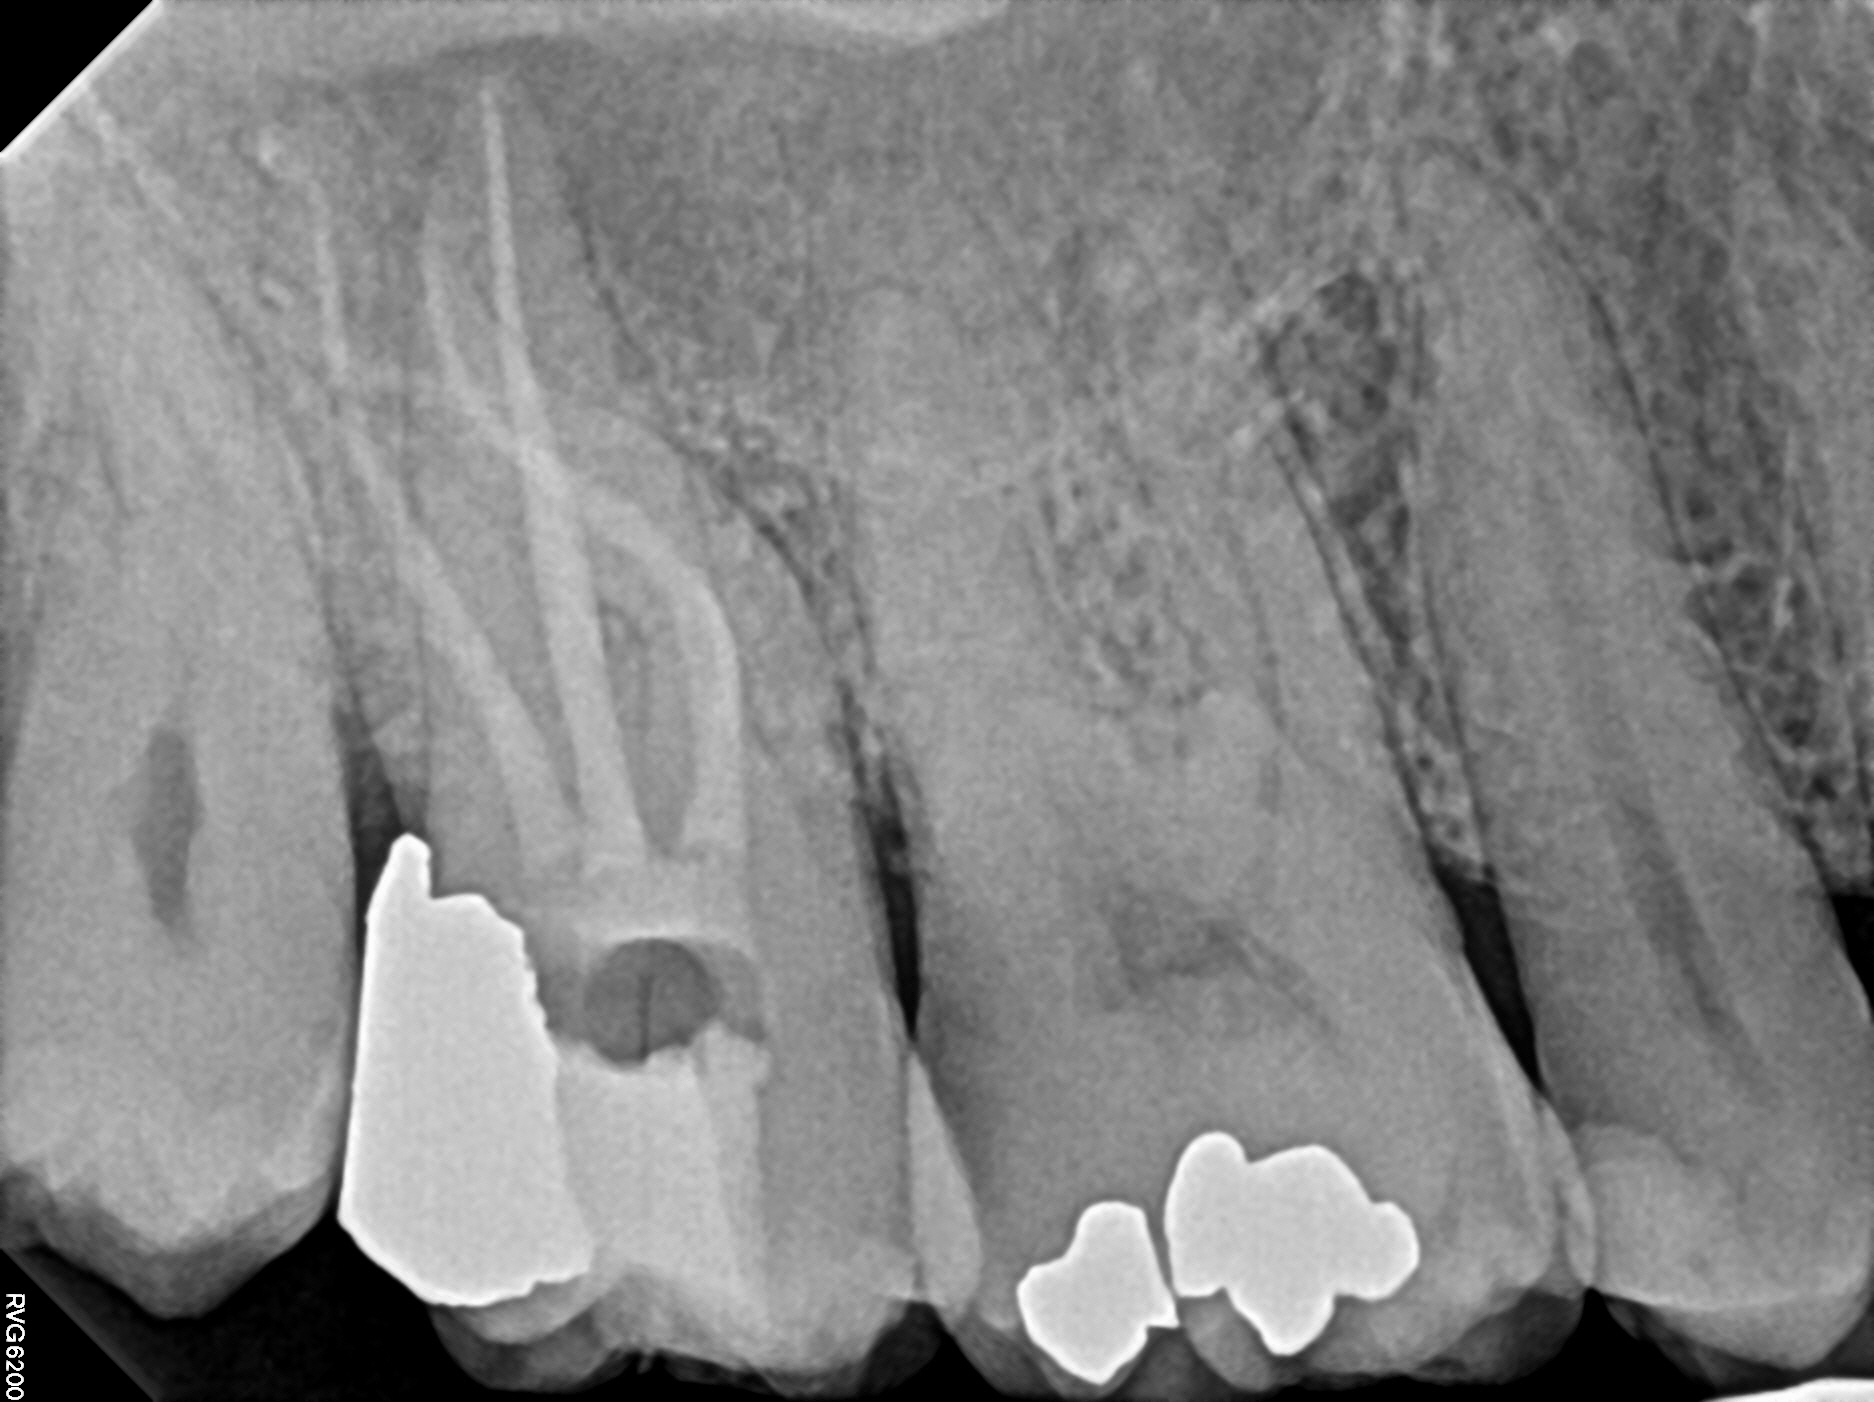

Case 10

This case also highlights curved roots. The first image is before treatment--notice the abscess in the bone (the dark shadows at the root tips). The second is during treatment and you can see the filling materials in the sharp curve of one of the roots. The third image is the immediate post-treatment image. The fourth image is one year later--notice the abscess (the dark shadows at the root tips) has healed. Unfortunately the tooth was never restored with a permanent filling or crown and the tooth had broken down further at this point and may need to be extracted despite the infection healing perfectly--it's critical to follow up with your general dentist for a final restoration!